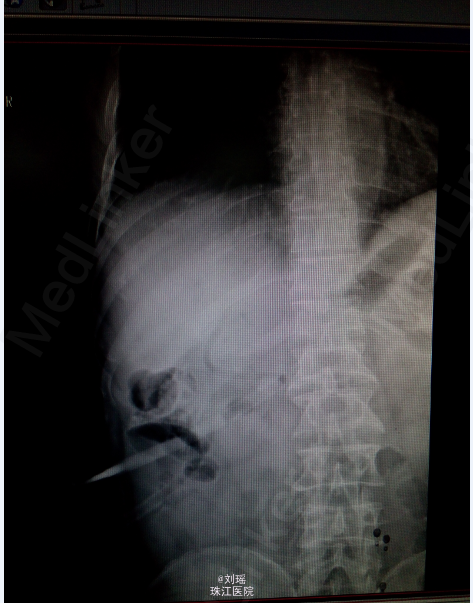

查体:生命体征平稳,慢性病容,皮肤巩膜重度黄染,右上腹T管,余无特殊。 辅助检查: 肝胆脾CT:右肾囊肿;胆总管粘液腺癌术后。 T管造影:胆总管全段可见不同程度,不同大小之充盈缺损并不同程度狭窄,考虑为占位性病变。肝内胆管明显扩张。